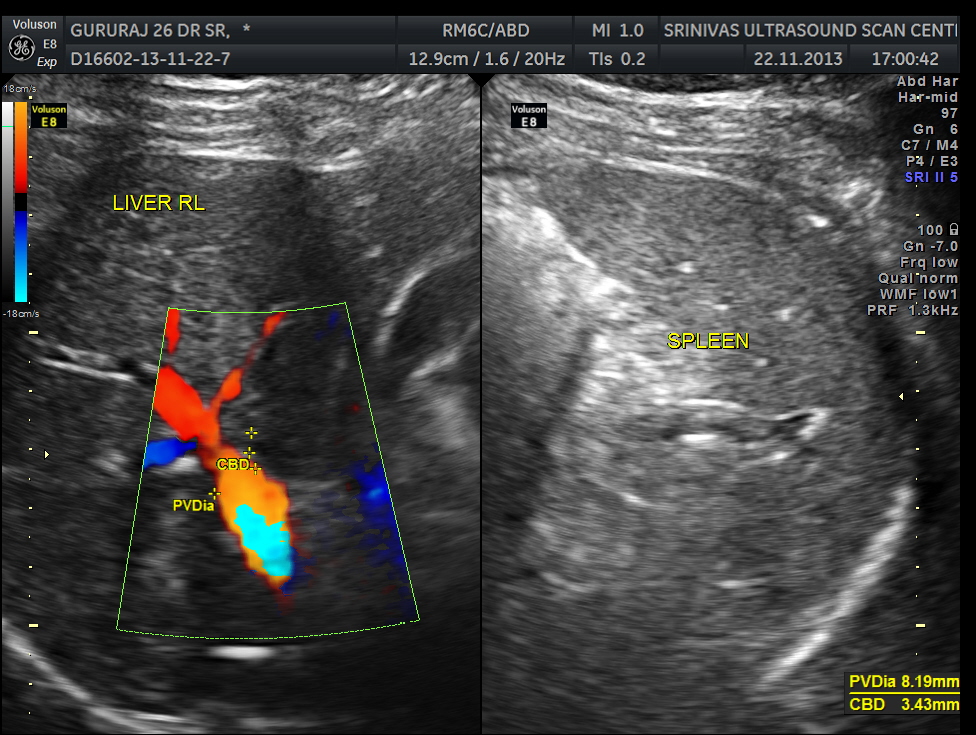

An ultrasound abdomen was done as part of evaluation of anemia.

Now for the unexpected findings . To finish off the scan , I was sweeping the aorta, IVC and the pre and post aortic regions.

The following image was obtained with the transducer in the mid epigastric region and an inch to the left of the mid line.